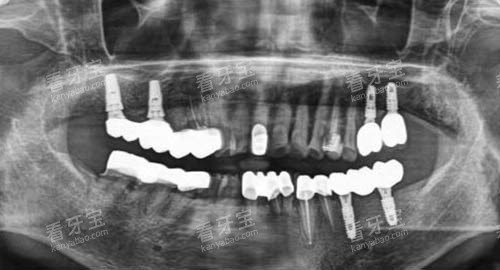

从硬件设施来看,该口腔机构引进了可靠的牙科诊疗设备,如智能化口腔全景机、种植机等。

这些设备能够为医生提供比较准的诊断依据,提高治疗的比较准性和效率。

例如,智能化口腔全景机可以快速、清晰地拍摄口腔全景图像,让医生齐全了解患者的口腔状况,为制定个性化的治疗方案提供有力支持。